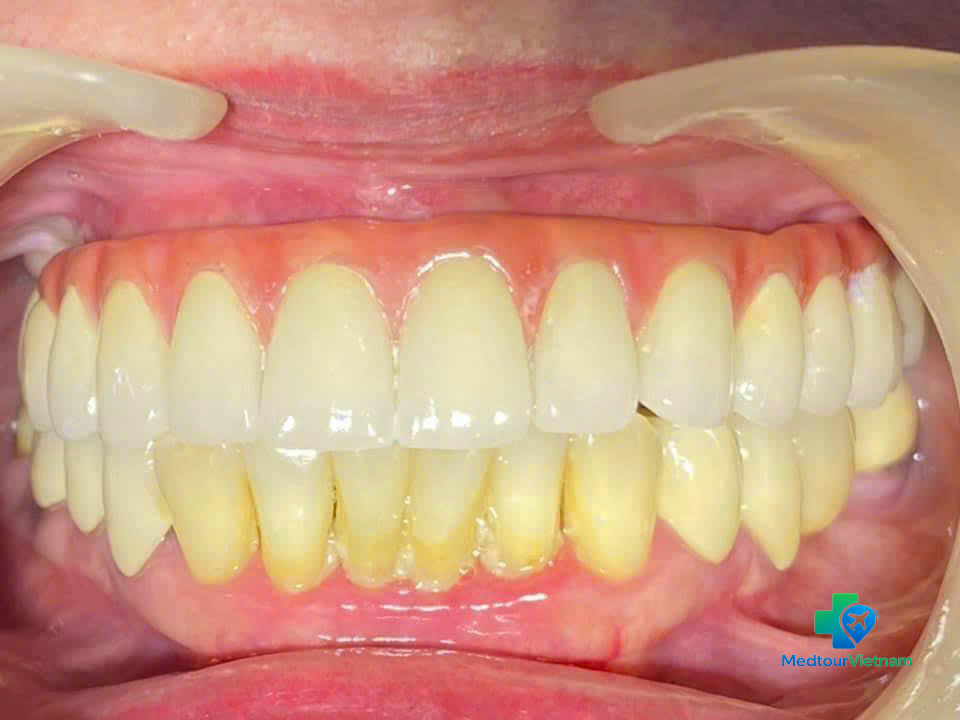

Step 4: Final Restoration

Placement of abutment and final crown

Bite adjustment and polishing

Final result of full mouth dental implants with natural-looking fixed teeth

Total Visits Required: Usually 2 visits (spaced 3–6 months apart) or a longer single stay depending on bone condition and treatment plan.